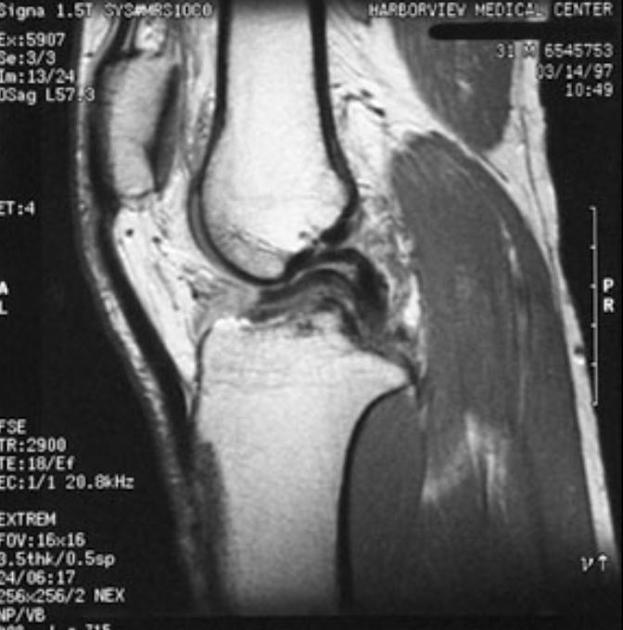

Diagnosis?

What must be intact for this appearance to occur?

Bucket handle meniscal tear (80% are medial meniscus). Highly specific but variable sensitivity for bucket handle tear.

The ACL must be intact for the tear to look like this- in order to prevent the fragment from migrating further laterally.